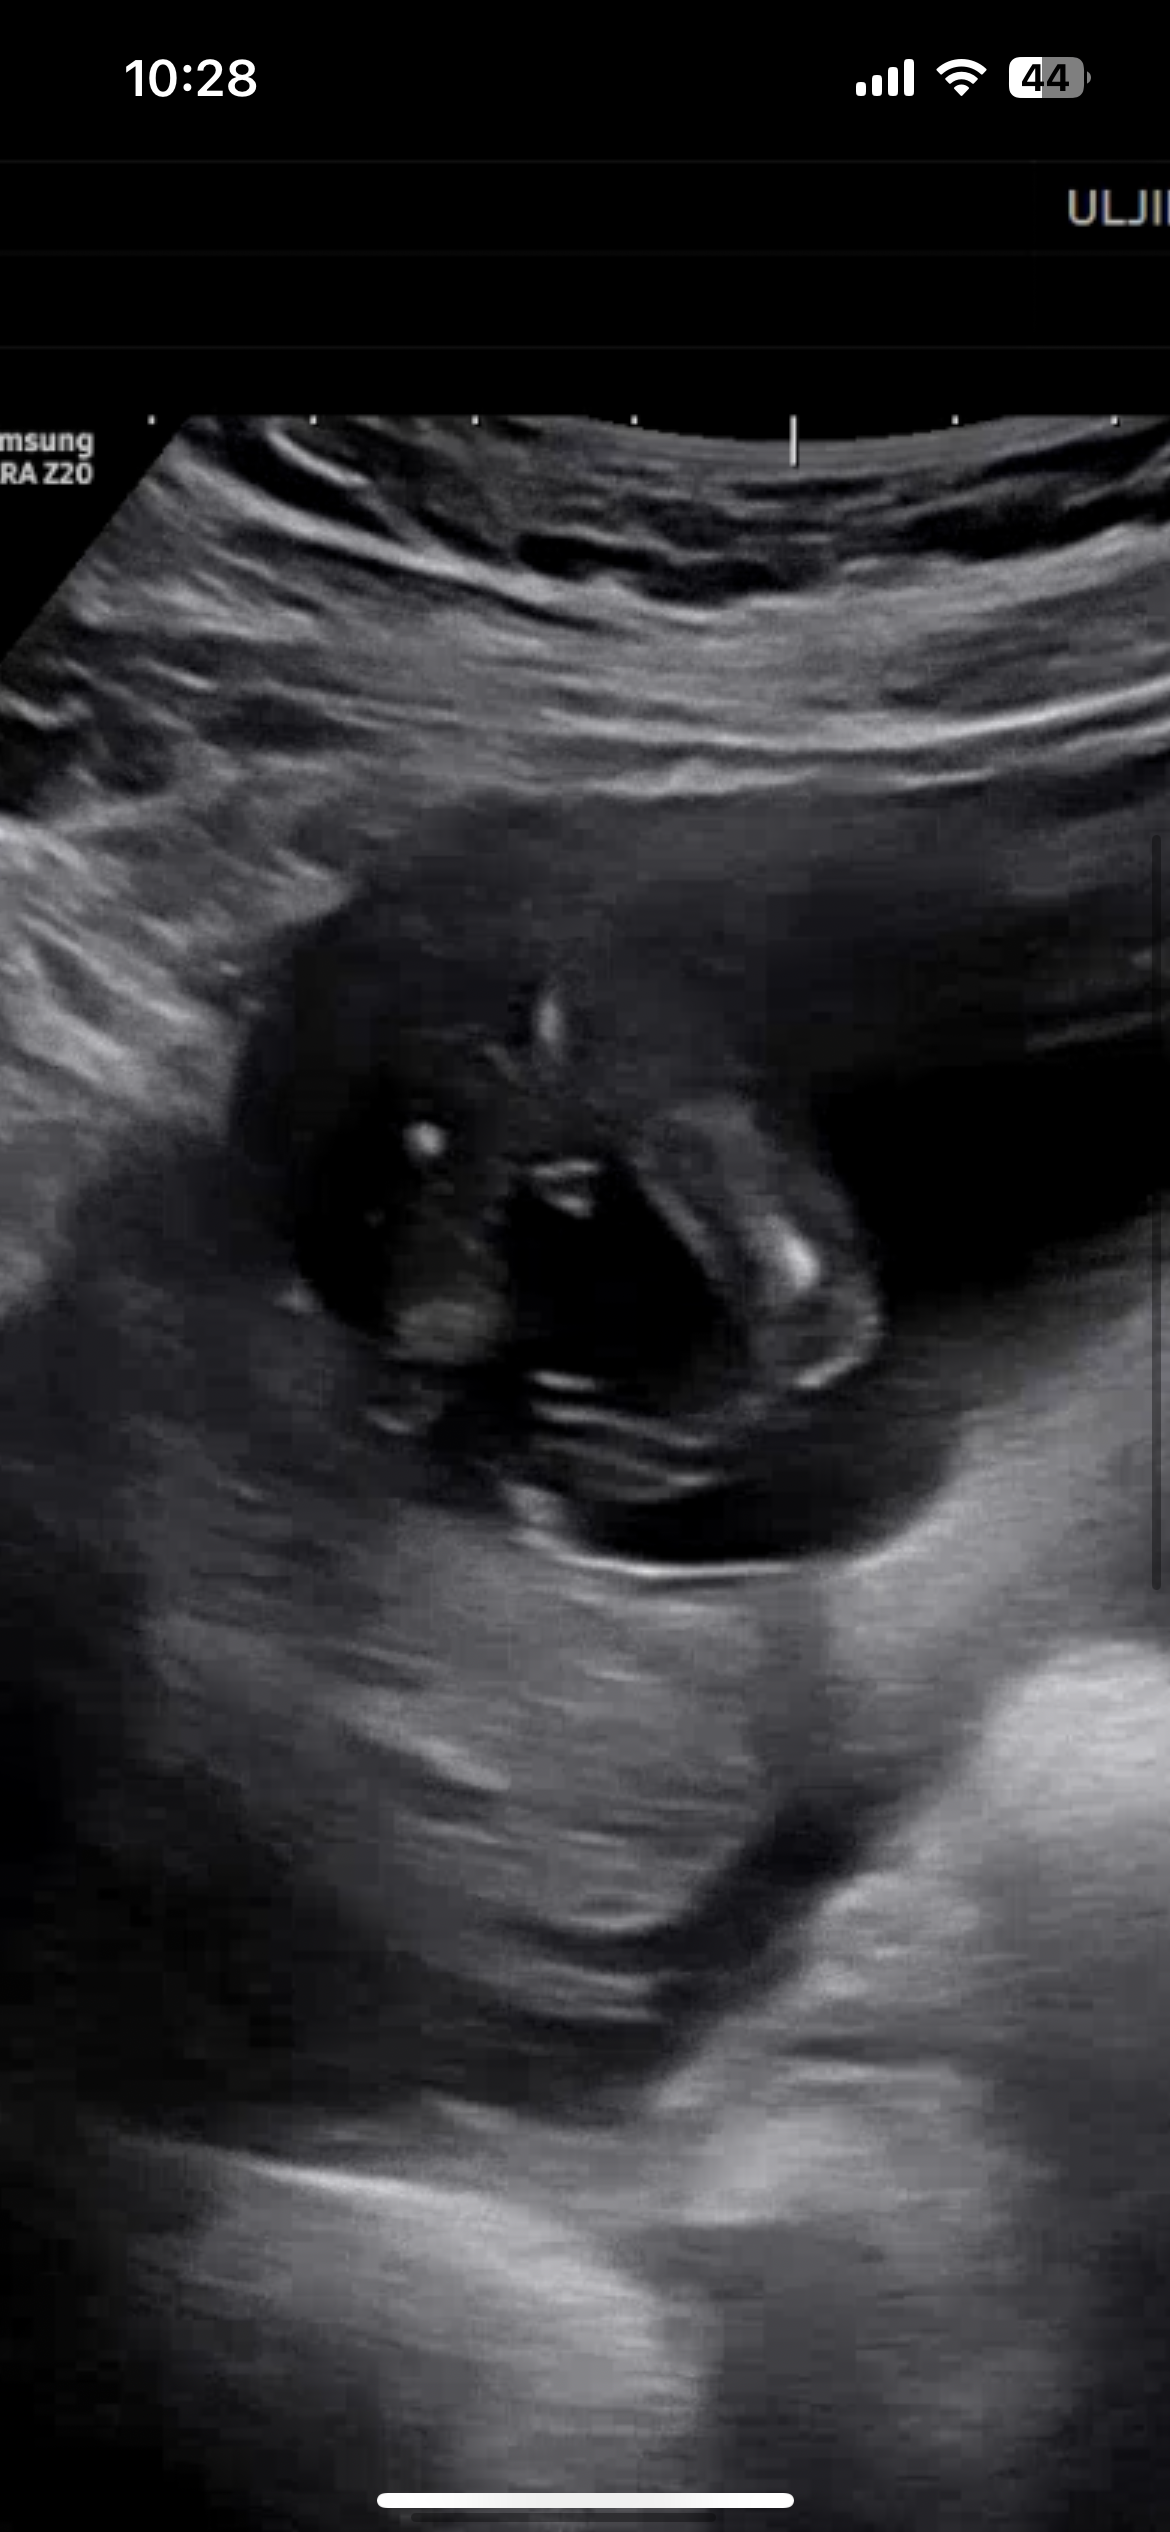

너무 완벽한 삼각점!

아들인거죠…??

14주0일… 바뀔 가능성 제로인가요…?? ㅎㅋㅎㅎ

삼각형이 너무 확실히 잘보이는... 아들같습니당!